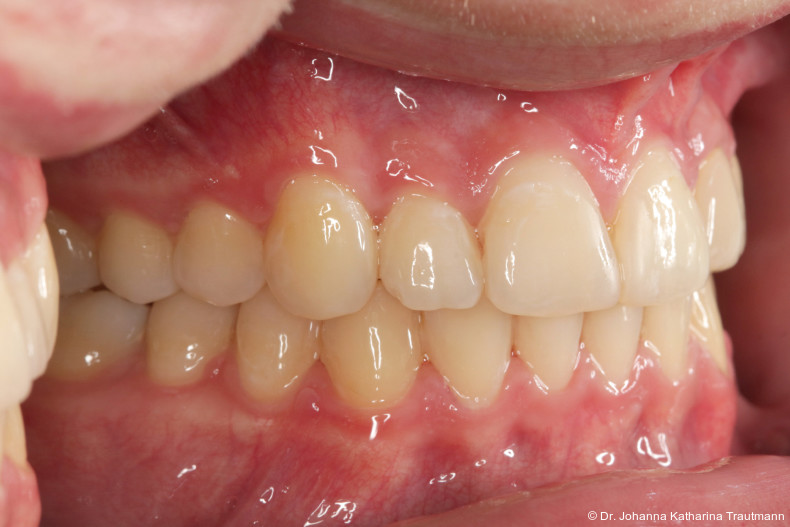

Längere Retentionszeiten ohne odontoplastischen Umbau können das Risiko eines Rezidivs des Zahnes 22 erhöhen. Dennoch ist häufig eine Abheilphase nach der Multibrackettherapie erforderlich, da sich gingivale Entzündungen oft erst nach ein bis drei Monaten vollständig zurückbilden.19–21 Um diesen Zeitraum zu überbrücken wurde an 22 die Kunststoffbasis der DVP (Doppel vorschubplatte) zur Retention sowohl mesial als auch distal extendiert. Schließlich wurden die Zähne 11, 21 und 22 kompositrestaurativ angeglichen, wodurch ein sehr gutes ästhetisches Ergebnis erzielt wer den konnte. Aufbauten mit Komposit bieten eine gute Möglichkeit, bei maximaler Schonung der Zahnhartsubstanz hypoplastische Zähne langfristig zu versorgen, und zeigten in ZehnJahresFollowups hohe Überlebensraten. Entscheidend ist hierbei eine ausgeglichene okklusale Lastverteilung, die mit hilfe einer physiologischen Frontzahnabstützung und gesicherten Okklusion durch die kieferorthopädische Vorbehandlung erreicht werden kann.22

Zur objektiven Quantifizierung des Behand lungsergebnisses wurde der Peer Assess ment Rating(PAR)Index erhoben.23 Im vorliegenden Fall konnte der PAR-Wert von 25 auf zwei reduziert werden, was einer Verbes serung von 92 Prozent entspricht und als hoch wertiges okklusales Ergebnis einzustufen ist.24 Zur Vorhersage der Langzeitstabilität bei Spalterkrankungen lässt sich dieser Fall in die Gruppe 1 des GOSLON Yardstick Index ein ordnen. Dieser sagt eine exzellente Langzeitstabilität vorher.25 Auch der Patient zeigte sich mit dem Ergebnis sehr zufrieden. Während der anderthalbjährigen Retentionsphase erfolgte zusätzlich eine ästhetische Nasenkorrektur zur Aufrichtung des linken Nasenflügels, wodurch neben der dentalen auch die extraorale Rehabilitation erfolgreich abgeschlossen werden konnte.